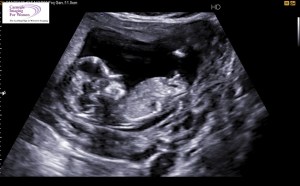

Superstitious to tell people or even dare to look at any nursery items online the first three months, with every sonogram, every blood test it would only just reaffirm him proving me wrong. He was sticking around and making himself comfy in there. I think it really hit me after my Maternit 21 and NT Ultrasound came back negative. It all became real and I’ll never forget that night in the living room, standing there on speaker phone with the doctor as she told us the good news on the test results and watching Chris stumble back into the wall with surprise hearing we were having a boy….It is one of the greatest, happiest moments in my life. I will never forget it.